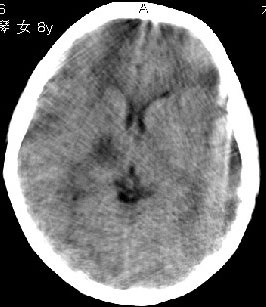

杨某,女,8y,家长述2006.10.13行破伤风疫苗注射后下肢疼痛,后自行粘贴膏药未见好转

,后续发现左上肢肢力下降。于2006.10.28在我院行ct检查,发现右侧基底节区片状低密度影,

无占位效应。ct值约:18~20hu。边界清晰,与相邻脑室无通连。未行增强扫描。余脑实质

未见异常。

支持adem的诊断。病史比较重要,其实左侧放射冠区白质亦见低密度,下面是我收到的一幅图片和英文资料。

右侧内囊后支、丘脑见片状低密度区,边界不清,无占位效应。

内囊后肢与丘脑区片状低密度影,无占位效应.

依据病史,首先考虑脑炎的可能性大,但星形细胞瘤(i级),脑梗不排除.